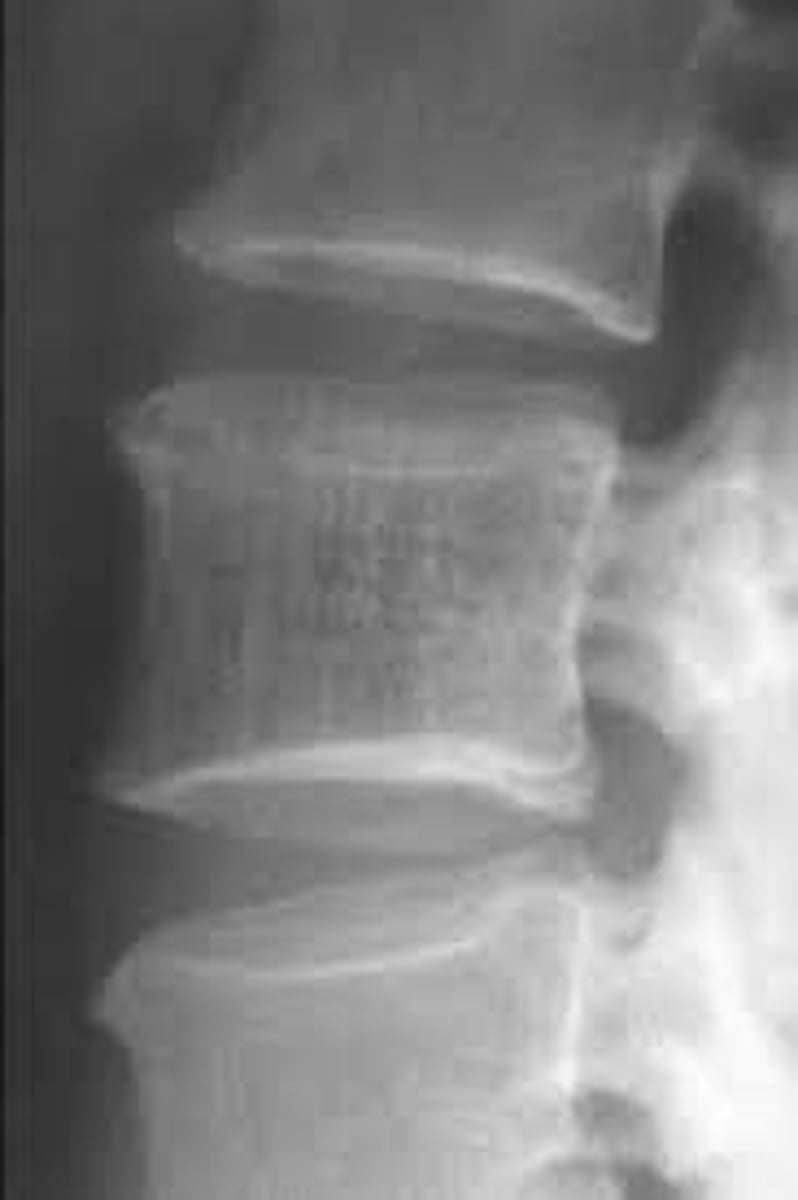

Objective Findings: Kemps + Diagnostic Imaging: X-ray